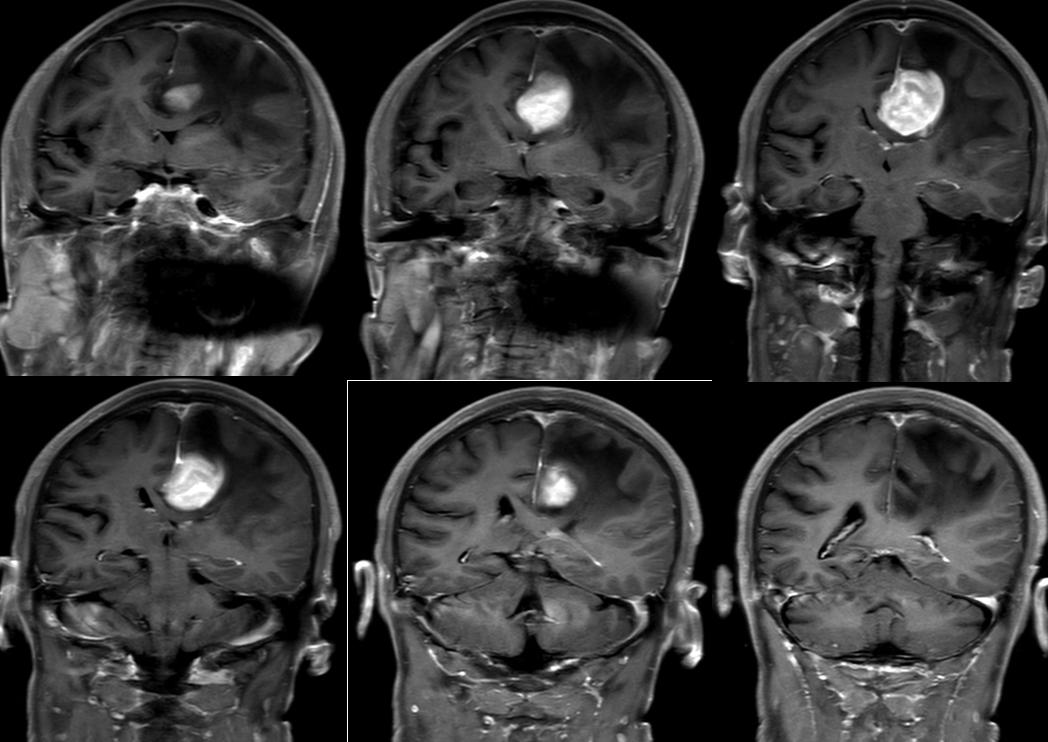

MRI:左侧颅底区可见金属伪影干扰。左侧额部大脑镰旁见一类圆形等长 T1 等长 T2异常信号T2 Flair 呈近等信号,中心见点状长T1短T2信号灶,病灶大小约3.3X3.7X3.cm,DWI(b=1000)及ADC 图示病灶轻度扩散受限,增强扫描呈明显不均匀强化,邻近部分硬脑膜可见线状强化,病灶周围脑实质见大片状长 T1 长 T2水肿信号,周围脑实质及双侧侧脑室受压变窄,左侧大脑半球脑沟裂变浅,中线结构右移。脑桥、双侧基底节区、双侧侧脑室旁白质、右侧放射冠及皮层下见多发斑点状、斑片状等长T1长T2异常信号灶,T2Flair 高信号,DMI未见明显扩散受限。右侧上颌窦粘膜增厚。

MRS示:病变区域Cho峰明显增高,NAA峰明显减低。

MRI:左侧额部大脑镰旁占位性病变,符合肿瘤 MRI表现,理学检查;脑膜源性肿瘤可能性大,请结合临床。

病理:淋巴瘤。